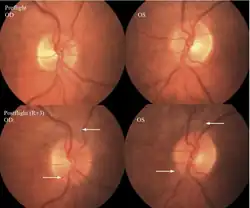

The seventh case of visual changes associated with spaceflight is significant in that it was eventually treated postflight. Approximately 2 months into the ISS mission, the astronaut reported a progressive decrease in his near and far acuity in both eyes. The ISS cabin pressure, CO2 and O2 levels were reported to be within normal operating limits and the astronaut was not exposed to any toxic substances. He never experienced losses in subjective best-corrected acuity, color vision or stereopsis. A fundus examination revealed a grade 1 bilateral optic-disc edema and choroidal folds (Figure 15).[5]

Figure 15: Preflight images of the right and left optic discs (upper). Postflight images of the ONH showing in more detail the extent of the edematous optic-disc margins and glutting of the superior and inferior nerve fiber layer axons OD and OS (arrows) (lower).